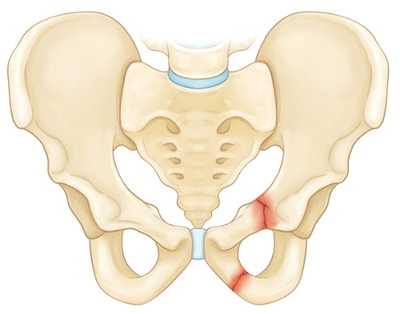

Перелом крыла подвздошной кости.

Перелом верхней и нижней ветвей лонной кости.

Нестабильные переломы. Данный тип переломов характеризуется нарушением целостности тазового кольца как минимум в двух точках, при котором анатомия таза, как правило, нарушается (происходит смещение фрагментов). Чаще всего такие переломы возникают вследствие высокоэнергетической травмы. К нестабильным переломам относят следующие:

Повреждение в результате передне-задней компрессии таза.

Вертикально-нестабильный перелом. При данном переломе одна половина таза смещается вверх.

Перелом в результате боковой компрессии. При данном типе перелома одна половина таза ротируется внутрь.

- Стабильные (переломы костей таза, не сопровождающиеся нарушением целостности тазового кольца). В эту группу входят изолированные и краевые переломы костей таза.

- Нестабильные (переломы костей таза, сопровождающиеся нарушением целостности тазового кольца). В зависимости от механизма травмы возможно возникновение вертикально нестабильных и вращательно нестабильных переломов. При вертикально нестабильных переломах костей таза целостность тазового кольца, как правило, нарушается в двух местах: в заднем и переднем отделе. Отломки смещаются в вертикальной плоскости. При вращательно (ротационно) нестабильных переломах со смещением смещение отломков происходит в горизонтальной плоскости.